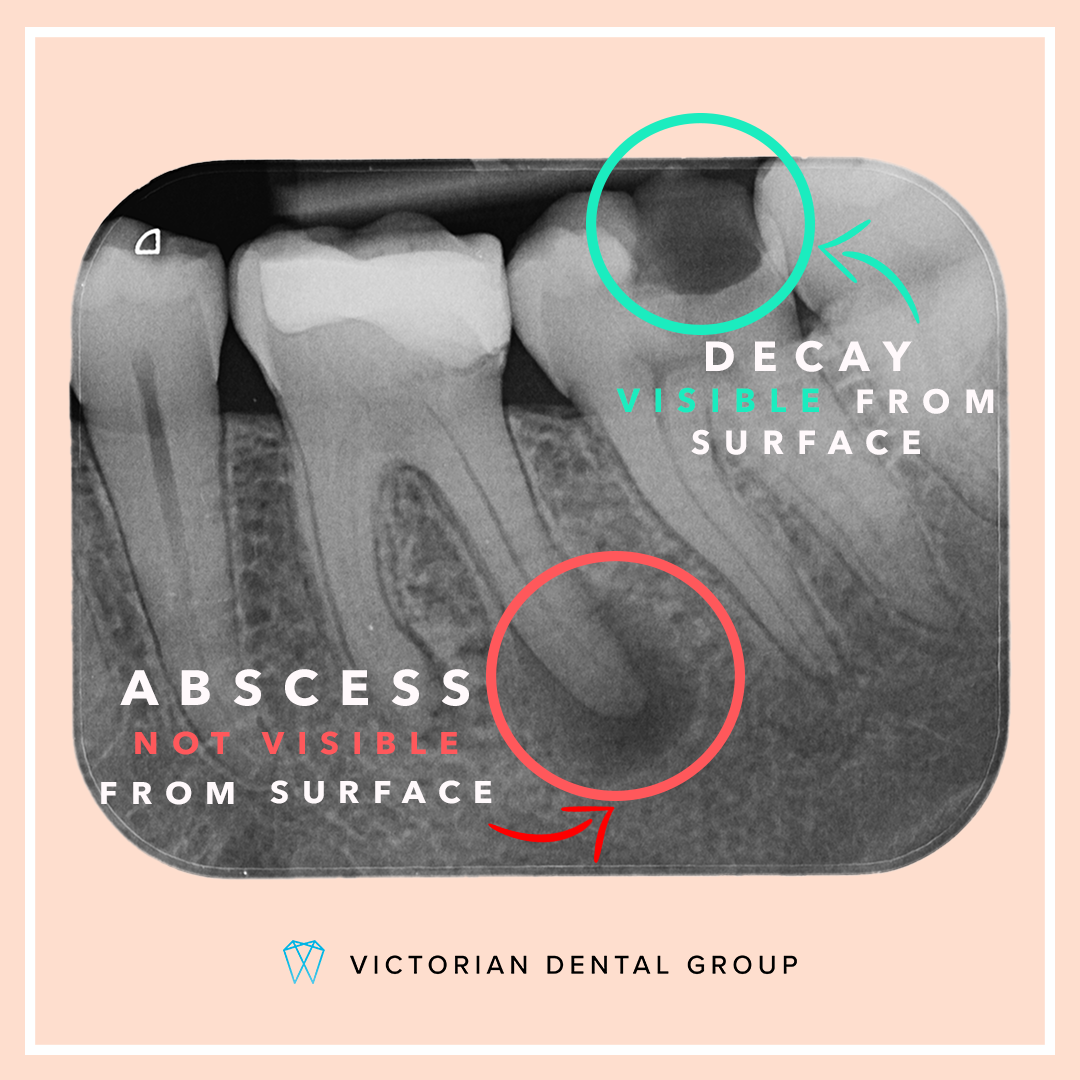

How to differentiate between Acute Alveolar Abscess and Periodontal Abscess